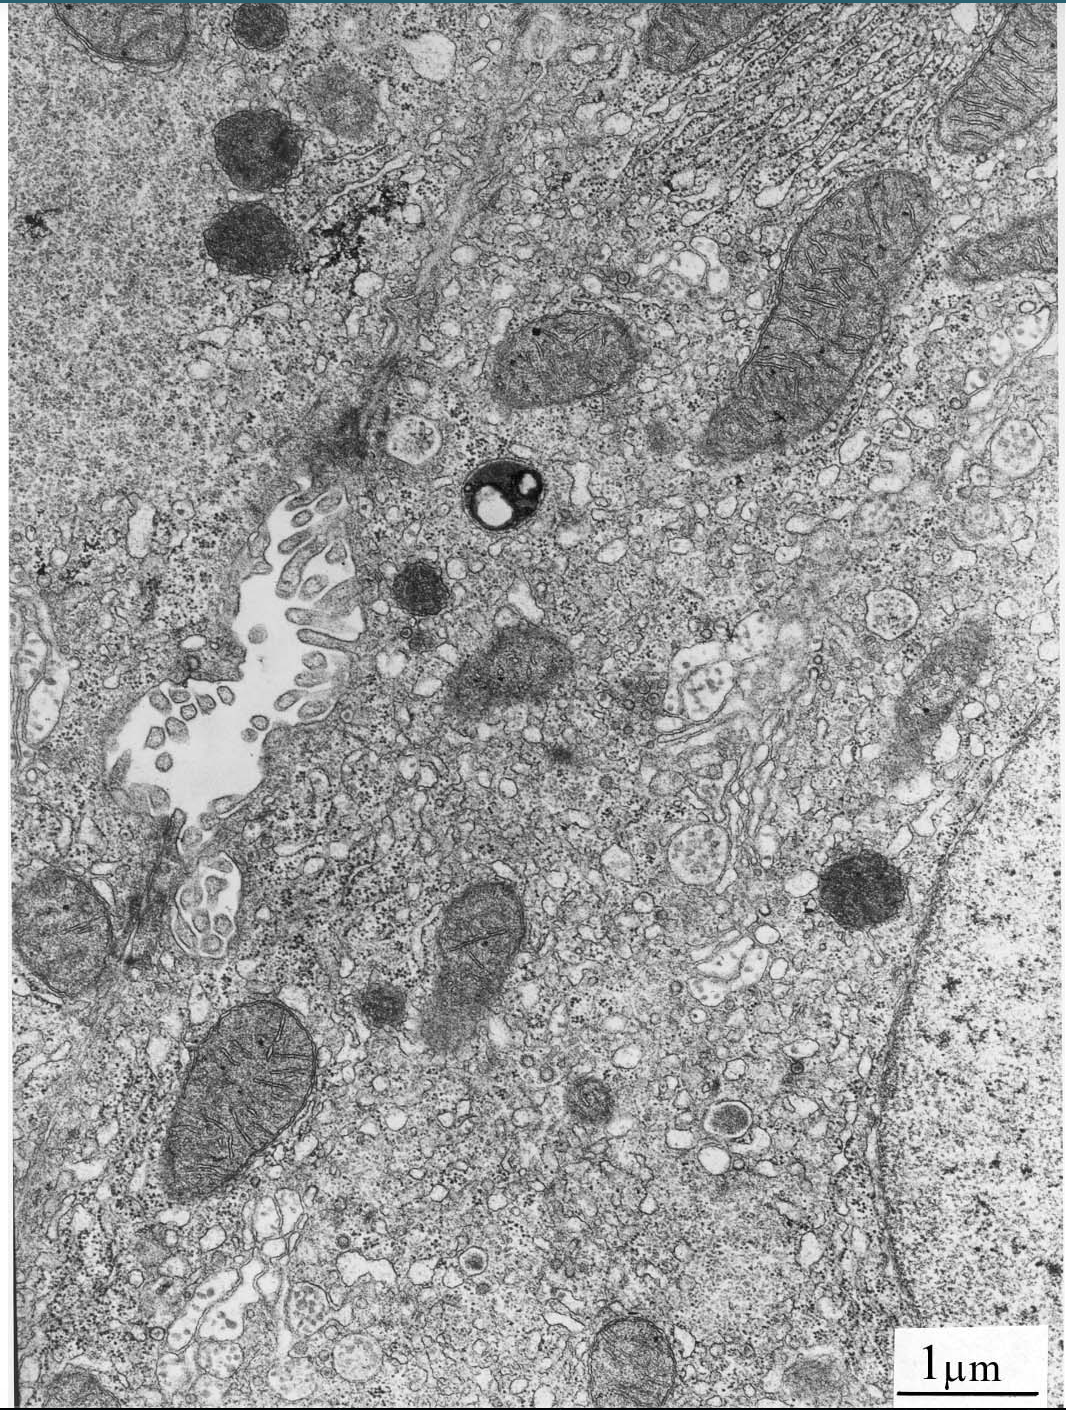

Part of Liver cell→ rat

Identify

The cell membrane

The nucleus and nuclear envelope

Rough and smooth endoplasmic reticulum

Ribosomes

Golgi apparatus

Mitochondria

Vesicles

Lysosomes

Glycogen granules

Add the drawing of these that identify what this is

Parietal (oxyntic) cell of the stomach– (rat)

Add the drawings of these!!